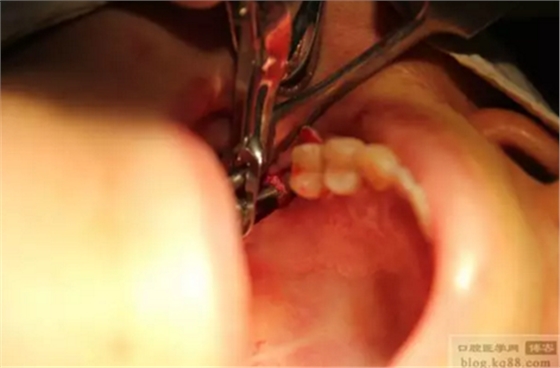

切開、定位。

鉆頭為OSS_TEM內(nèi)提升盤鉆。